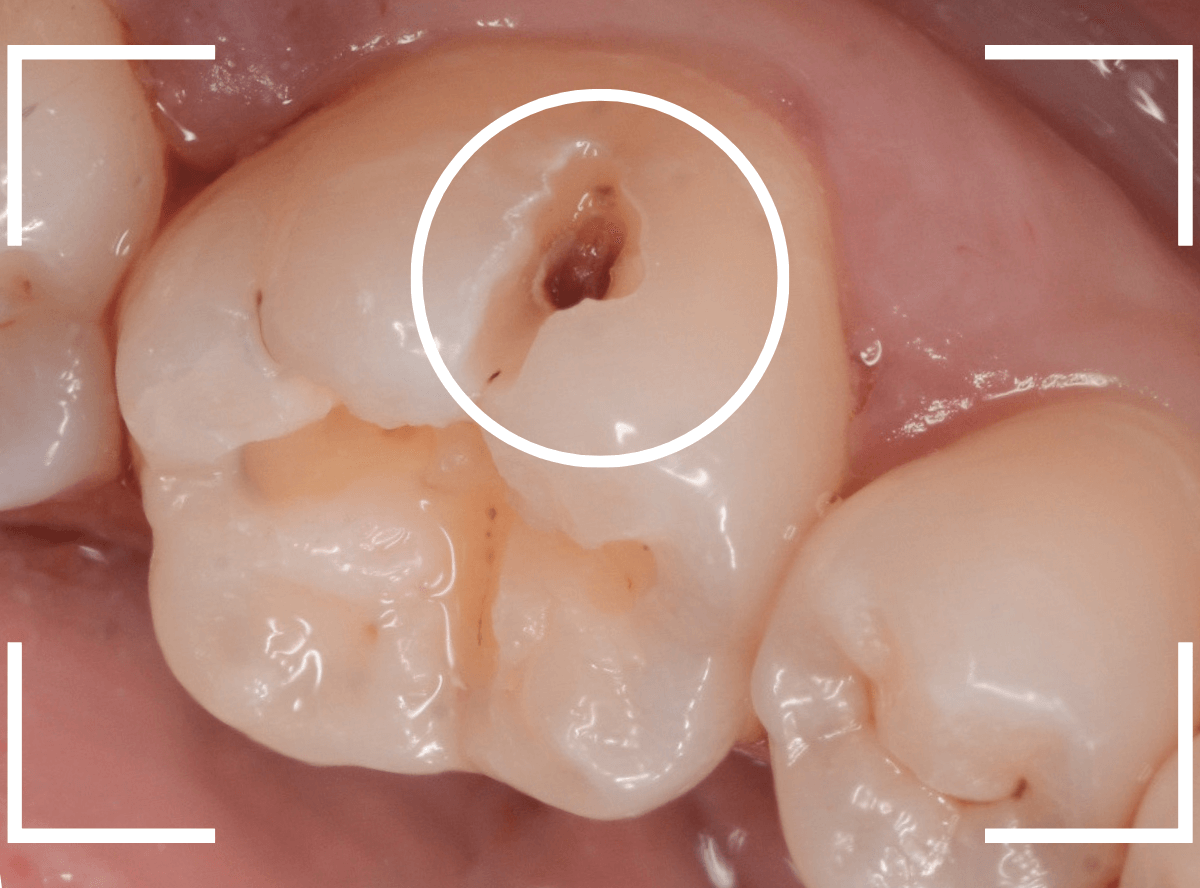

Case.9 レントゲン写真で写らない側面の虫歯

歯の側面が大きな虫歯になってしまった患者さんのケースです。

このように歯の側面が虫歯になった場合、レントゲン写真で虫歯の状況がはっきりわからない事が多いです。

レントゲン写真では、あまり大きな虫歯のようには見えません。

治療を開始します。

歯を少し削ると、すぐに大きな虫歯の穴が出てきました。

さらに虫歯を削ります。

神経に触れてしまいそうなほど、深くて広い虫歯ですね。

全ての虫歯を除去したところです。

何とか神経に触れる寸前のところで踏みとどまれましたが、レントゲン写真からは想像できない虫歯の深さでした。

繰り返しになりますが、虫歯の治療も奥が深く、長年歯科治療をしている我々でも診断に苦慮する場合があります。

くれぐれも、自己判断はせずに、定期メンテナンスに来てくださいね。